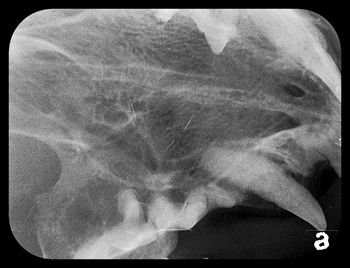

Feline dental implant

Figure 4A: Push-in implant being tapped into osteotomy site

Figure 4B: Bone graft material around implant

Fig 4C: With wound sutured

Pictures shown are cases presented by Rocco Mele, DVM, of Tucson, Arizona, depicting a successful upper fourth premolar extraction, implant placement and bone graft performed on a dog at the same time and a second case of a canine extraction, implant and bone graft at the same time in a cat.